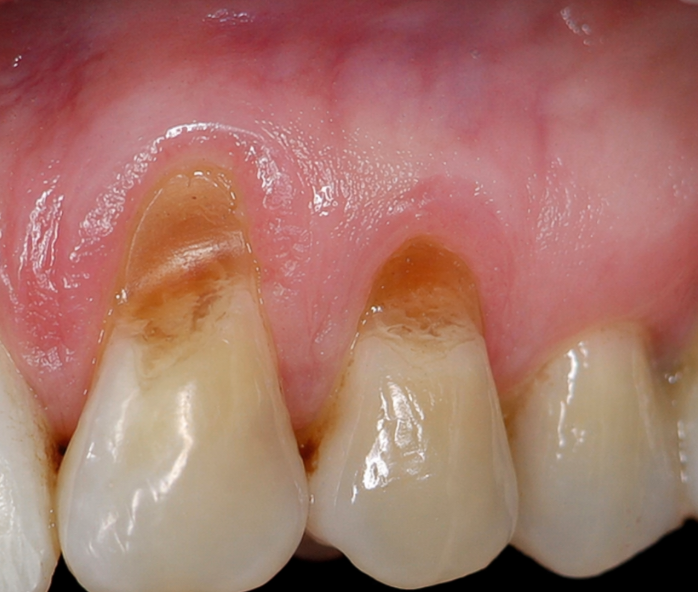

Клиновидный дефект

Клиновидный дефект - когда разрушается сам зуб

Клиновидный дефект - это уже не про десну, а про сам зуб.

В области шейки, ближе к десне, появляется характерное углубление - «ямка» с плотными, чёткими краями. Это не кариес и не инфекция. Зуб в этом месте не разрушается бактериями - он постепенно теряет ткань под действием внешних факторов.

Чаще всего это сочетание нескольких причин: механическое воздействие, химическая среда и нагрузка.